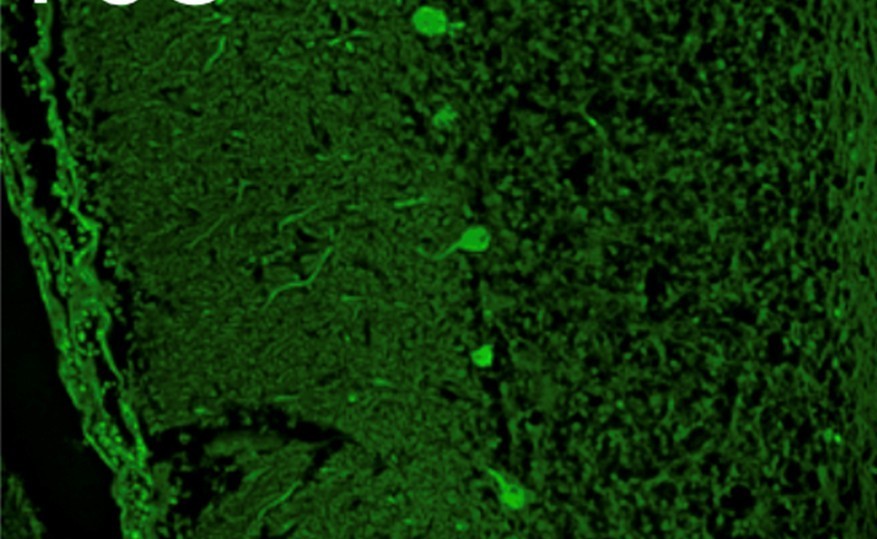

病理学的並びに分子病理学的手法を用いた疾患診断および病態解明

研究内容の特徴

帯広畜産大学が酪農・畜産地帯に位置することから、動物、特に産業動物の自然発生疾患に対する病理診断を日々行っています。その中から、新規あるいは稀有な病態を見出し、それら病態についての病理学的な研究を行うとともに、既知の病態の未解明の事象の解明に取り組んでいます。また、病理診断に分子生物学的手法を応用するための研究や、学内外の基礎・臨床研究分野の多くの先生と様々な共同研究も行っています。